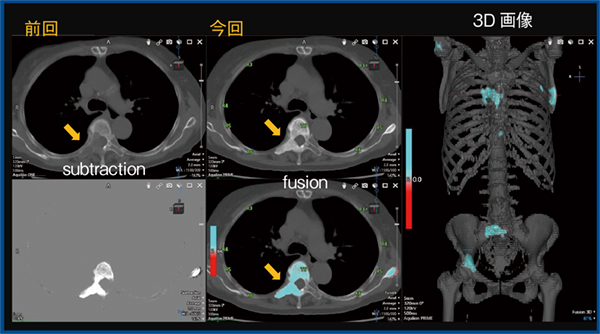

TSBの技術的な特徴としては,骨領域識別処理,線形・非線形位置合わせ処理による精度の高い差分処理,骨ランドマーク情報を活用した肋骨・椎体番号の位置同定処理が挙げられる。TSBのFindings Workflowでは,画面左上に過去と今回の2D画像,下段にサブトラクション画像とフュージョン画像,右側に3D画像が表示される(図1)。骨の変化については,前回と比較して濃度が上昇した部位は青色,低下した部位は赤色で表示される。3D画像の任意の部位をクリックすることで,対応する2D画像の断面が表示され,詳細な観察が可能になる。また,矢状断像や冠状断像に切り替えての同様な観察も可能である。TSBの骨ナンバリング機能では,肋骨や椎体の番号が2D画像のスクロールに追従して表示され,これらは矢状断像や冠状断像でも同様に表示される。

図1 肺がん,多発骨転移

1.肺がん,多発骨転移

通常の読影では,横断像をスクロールしながら,過去画像と比較して観察を行う。横断像では,椎体は比較的視野の中心にあり観察しやすいが,肋骨や肩甲骨,大腿骨などは視野の辺縁部に位置しているため,観察が不十分になる可能性がある。また,肋骨はその形状からスクロールに従って視点を動かしながら観察する必要があり,骨全体を細かく観察するには時間がかかり,見逃しが生じる可能性がある。図1は,肺がん,多発骨転移症例のTSBの画面であるが,3D画像で骨の濃度が上昇した領域が青く表示され,前回画像と比較することで新たに出現した硬化性転移であることがわかる。従来通りの画像評価は必要となるものの,TSBを併用することで見逃しの防止や全体の変化を俯瞰して観察することが可能である。